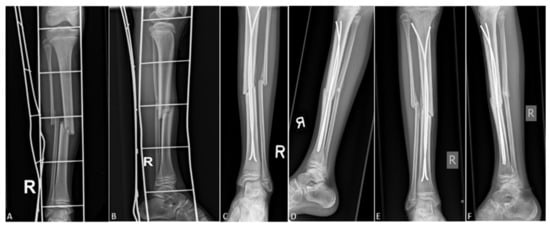

On the first postoperative day, strict rest is required, mostly due to pain control. From the second or third postoperative day (individually, depending on age and other factors, such as general condition of the patient or associated injuries), physical therapy and getting out of bed with crutches begins. After the patient learns to walk stably using crutches, if the other parameters are satisfactory, the patient is discharged to home care, continued with ambulatory physical therapy after discharge. For the first three or four weeks, the patient does not step on the operated leg, and then, after radiological verification of the fracture, begins gradual weight bearing. For the first few days, the bearing is approximately one-seventh of the body weight, after which the bearing gradually increases. On average, after 8 to 10 weeks of osteosynthesis, after radiologically verifying a good callus, a crutch-free gait begins. Each patient underwent an intraoperative X-ray after repositioning the bone fragments and placing of titanium elastic nails. Control X-rays were taken seven days after the procedure, and after one, three, and six months, or until healing of the bone was completed (Figure 1). Radiological evaluation was carried out using standard AP and LL radiographs at each visit to evaluate the consolidation of the fracture and identify complications such as secondary displacement, shortening, nail migration, delayed union, nonunion or malunion, and re-fracture (Figure 2). Nonunion was defined as the lack of appropriate healing within six months from index surgery. Malunion was defined as angular deformity of greater than 5–10° (depending on patient’s age) in the coronal or sagittal plane. Limb length inequality >1 cm was considered as limb shortening. All nails were removed under general anesthesia when the radiological healing was evident at the median of six months.

Figure 2. Displaced distal tibial fracture in 9-year-old male patient: (A) preoperative AP radiograph; (B) preoperative LL radiograph; (C) AP radiograph one month after surgery; (D) LL radiograph one month after surgery; (E) AP radiograph three months after surgery; (F) LL radiograph three months after surgery.